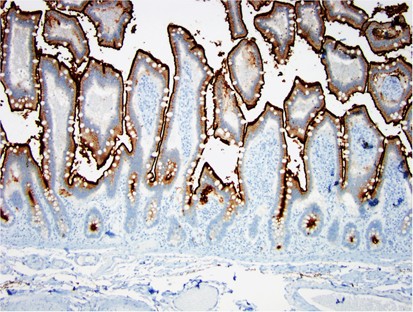

In total, 103 specimens were retrieved and stained with CD10 (35 colonic and 68 enteric). All 35 colons (100%) were negative for CD10, regardless of clinical setting (five normal, six colostomies, five colonic anastomoses, six ulcerative colitis, five diversion colitis, and eight Crohn's colitis), and whether or not they were actively inflamed. All normal small intestines (6/6; 100%) and normal ileocecal valves (3/3; 100%) had uniformly positive CD10 staining of the enteric mucosa (Figure 1). Surgically altered small intestinal specimens from patients without inflammatory bowel disease had patchy loss of CD10 staining in 5/25 cases (20%). Specifically, there were 12 ileostomies, 6 enteroenteric anastomoses, and 7 enterocolic anastomoses, all of which came from patients without inflammatory bowel disease. Of these, one ileostomy (8%), one enteroenteric anastomosis (17%), and three enterocolic anastomoses (43%) had patchy staining, all with loss of CD10 expression on ≤10% of the epithelium (Figure 2). The ileostomy and the enteroenteric anastomosis with loss of staining both had active inflammation, while one of the three enterocolic anastomoses was actively inflamed.